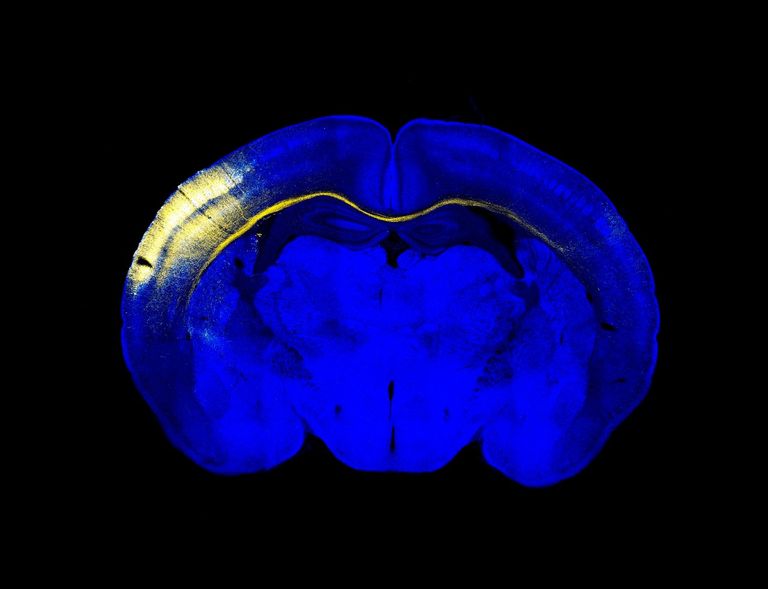

وهذه المنطقة تقع أسفل الفصين الصدغيين، وتُعرف باسم "التلفيف المسنن"، وتتكون من نوع خاص من خلايا الدماغ التي تشارك في اكتساب ذكريات جديدة وفي التعلم.

السبب الأول هو أن "التلفيف المسنن" يتلف لدى المصابين بمرض ألزهايمر، لذا فإن معرفة أكبر بهذا الهيكل وتطوره قد تساعد في الكشف عن هذا المرض التنكسي العصبي مبكراً، وكذلك تطوير علاجات جديدة لعلاجه.

أما السبب الثاني فهو أن الخلايا العصبية للحصين تحظى بأهمية بالنسبة للأبحاث الطبية، لأن الخلايا العصبية التي تولد في الحصين من نوع خاص، وكان معروفاً أنها تشارك في عملية اكتساب ذكريات وفي التعلم في الفئران المعملية، ولكن كانت هناك شكوك حول وجود مثل هذه الخلايا في الدماغ البشري البالغ، لأن أبحاثاً أخرى حديثة لم تكتشفها.

اكتشاف واعد بالنسبة لألزهايمر كما تحلل الدراسة عن طريق مقارنة الخلايا العصبية للحصين في أدمغة مجموعة من 13 فرداً أصحاء و45 مريضاً بمرض ألزهايمر، وتكتشف أن عدد الخلايا العصبية الجديدة ينخفض بشكل كبير في المراحل الأولية من المرض ليواصل الانخفاض التدريجي مع تقدمه.